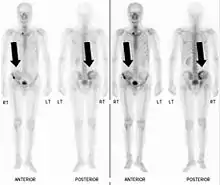

Scintigraphie corps entier avec 99mTc-HDP de la patiente avec une fracture du bras due à une métastase du cancer du sein